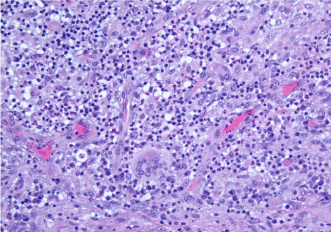

A four-week course of high-dose steroids was completed with near-complete resolution of the palpable lesion and clinical symptoms. The residual lesion was excised completely (Figure 3) with negative margins. Histopathology (Figure 4) was consistent with the previous biopsy and confirmed diagnosis of IGM. The patient remains asymptomatic 10 months after surgery.

Figure 4. Surgical pathology: Multinucleated giant cells, epithelioid histiocytes, and lymphocytic infiltrate forming non-caseating granulomas around ducts and lobules